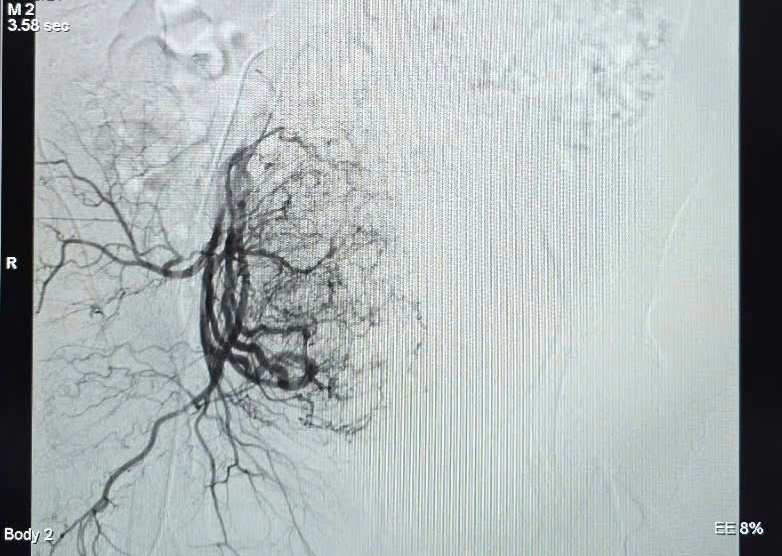

Hình ảnh tăng sinh mạch máu trước can thiệp. |

Ê-kíp can thiệp do BSCKI Trần Công Khánh, Phó khoa Chẩn đoán hình ảnh đã thực hiện thủ thuật nút mạch tử cung bằng keo sinh học. Hình ảnh chụp cho thấy tử cung được cấp máu chủ yếu từ động mạch chậu trong phải với nhiều nhánh tăng sinh mạch; sau khi xác định vị trí chảy máu, ê-kíp tiến hành tắc mạch thành công sau 45 phút.